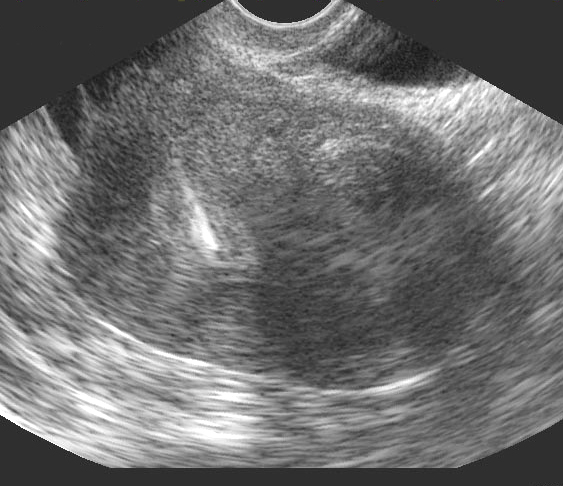

Utérus en coupe sagittale. Myome intra-mural sous-séreux. DIU en place (Cliché : Dr. C. TALMANT)